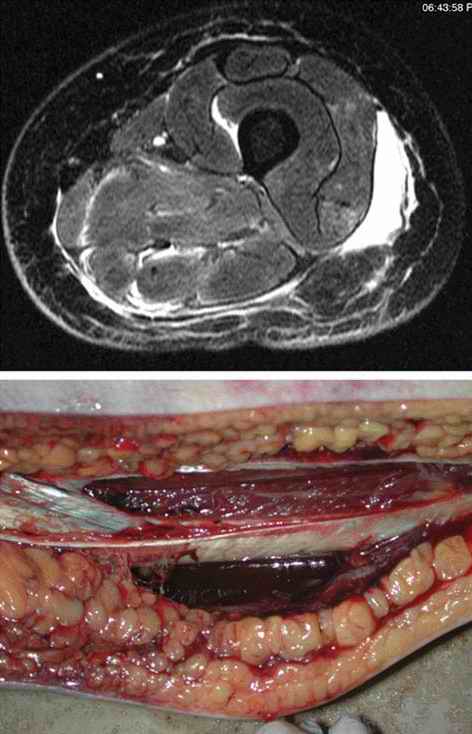

In previous studies [4], magnetic resonance imaging (MRI) proved to be a sufficiently sensitive method to detect softissue injuries. As subcutaneous hematomas and trauma of the fatty tissue are forensically relevant as to energy and impactpoint reconstruction, Yen et al. [5] evaluated such traumatic effects and graded them into four categories, namely, I-IV. All these stages or categories were clearly seen in MRI. The mildest stage is I, in which only a perilobular hemorrhage is seen. Stage II implies a contusion of the fat and stage III a disintegration of the fat lobules. The most severe form of fatty-tissue injury is stage IV. In this stage, which is the result of an enormous local force against a body part, not only are fat lobules disintegrated, but also a subcutaneous cavity is encountered. Usually, the entire body has to be skinned at autopsy to assess the existence and the extent of such typical signs of blunt trauma. As Yen et al. have shown, postmortem MRI is a viable tool for such an assessment (Figure (Figure D3.2.4 and Figure (Figure D3.2.5). This technique is especially valuable in examining surviving victims of blunt trauma, where a pathological analysis is not possible.

The next deeper structure of the body, namely the musculature, may also be injured in blunt injuries. Their injury implies that a greater energy was involved than necessary to merely crush the fat lobules of the subcutaneous fatty tissue. Hemorrhages into the muscles are hard to detect but are readily visible in MRI (Figure Figure D3.2.6). Furthermore, a crushing of the muscle, an indicator that a considerable local force was applied, can also be visualized in MRI.

As is well known from clinical medicine, mid-face fractures can also extend over the maxilla and the zygomatic bone (Figure D3.2.8). These fractures arise from a direct impact to the face. Depending on the involved structures, these fractures are classified as Le Fort I-III. This classification can be difficult, especially in cases of vehicle accidents, where, due to the massive damage, multiple fractures are often seen. In such cases, the Le Fort classes overlap (Figure D3.2.9). Mandibular fractures occur due to punches, falls, and vehicle accidents, to name just a few mechanisms. Direct fractures are seen paramedially, whereas indirect fractures are mostly located in the region of the joint and the mandibular body.

![]() |

In cases of strangling or throttling, a limited amount of pressure is exerted onto the cervical vessels, thus giving rise to petechial hemorrhages. However, they are rarely encountered in cases of classic suicidal hanging. In these cases, the afferent and efferent blood vessels to the head are typically-if the noose is behind the mandibular angle-equally compressed. Therefore, no petechial hemorrhages are to be expected. Here, a thorough medicolegal inspection can reveal telltale imprints to the neck, even if the noose has been removed. Slight and superficial abrasions of the skin can often lead to the correct diagnosis. Additional hemorrhages of the subcutaneous tissue and the cervical musculature can, according to our experience, further support this hypothesis (Figure D3.2.18), although recent literature is uncertain as to the overall significance [17,18]. Furthermore, fractures of the hyoid bone or thyroid horns, a finding easily detected in postmortem MSCT (Figure D3.2.19 and Figure D3.2.20), give rise to the diagnosis blunt trauma to the neck [19,20].